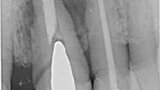

Fig. 8: Postoperative radiograph of implant placement.